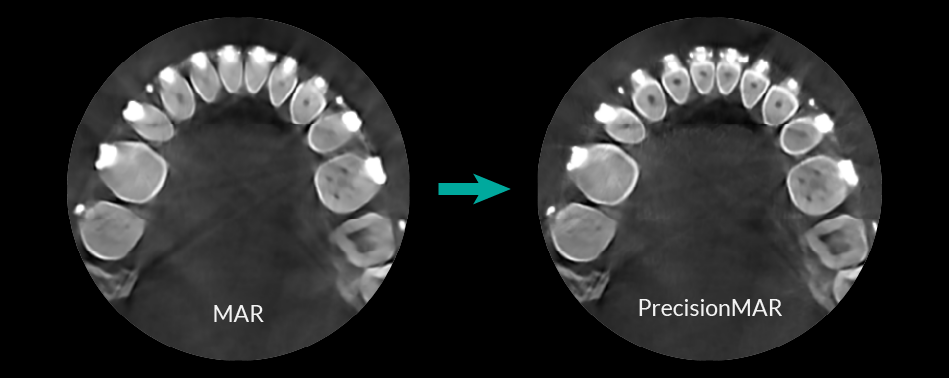

Minimized Metal Artifacts

PrecisionMAR (Metal Artifacts Reduction) allows for greater diagnostic accuracy by significantly reducing metal artifact